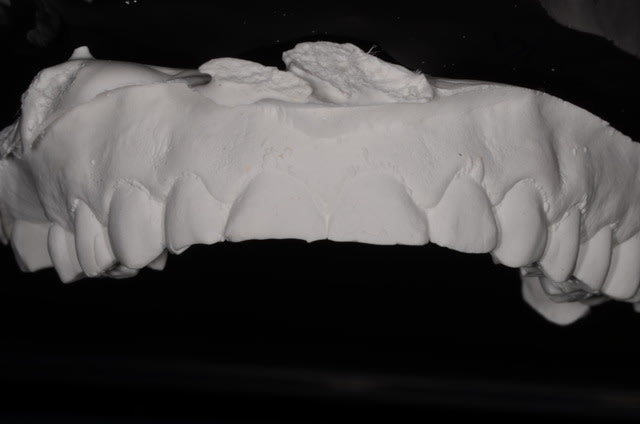

après avoir bien galéré avec la version 3.85 je mets en ligne un cas de 6 cérams faites à partir des modèles scannés avec cerec.

D'abord les biscuits, modèles d'origine (2005), situation actuelle, puis couronnes glacées.

Blocs VITA Triluxe Forte 12.